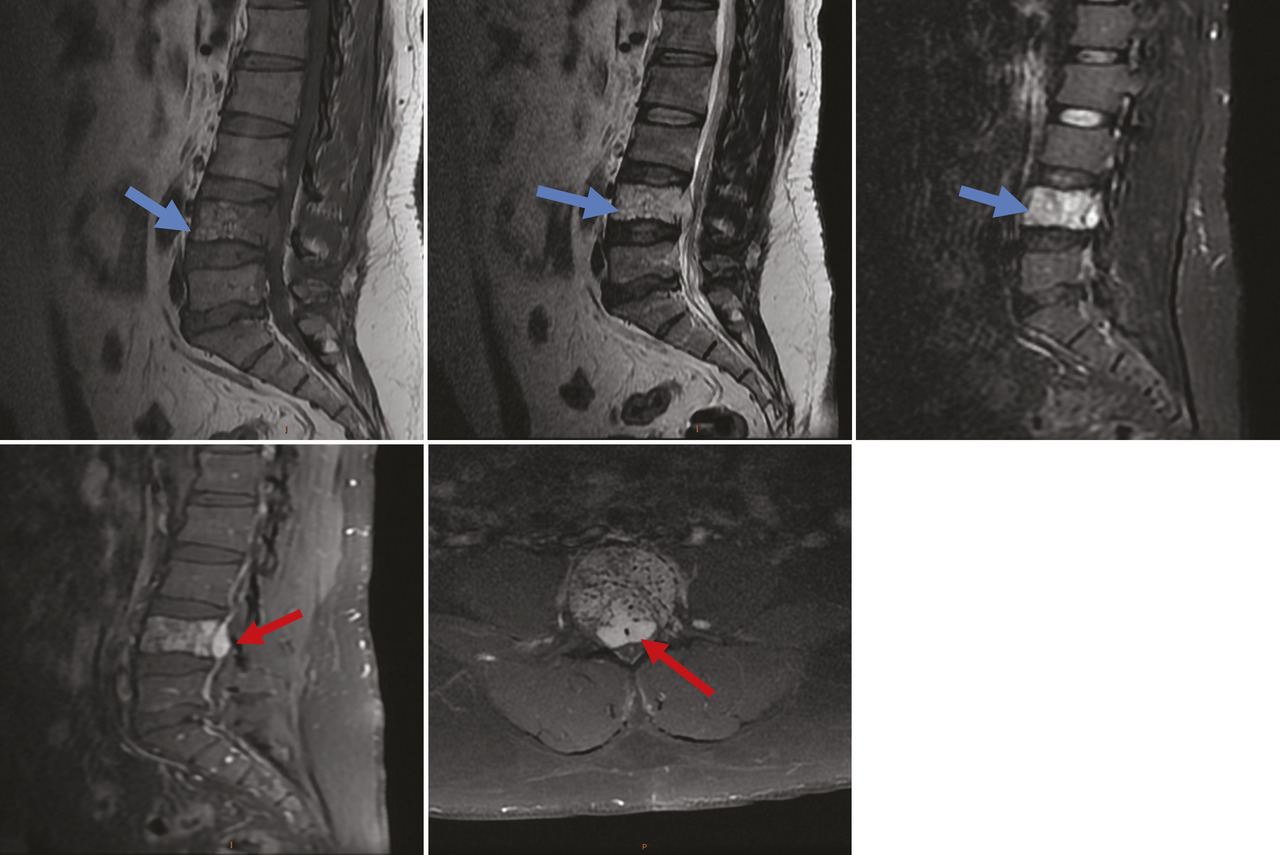

Un homme âgé de 42 ans, sans antécédents notables, souffre depuis un an de lombosciatalgies bilatérales d’aggravation progressive, avec installation, depuis trois jours, de troubles génitosphinctériens à type de rétention urinaire évoluant dans un contexte d’apyrexie et de conservation de l’état général. À l’examen clinique, le patient est conscient, stable sur le plan hémodynamique et respiratoire. L’examen neurologique objective une parésie des deux membres inférieurs avec des réflexes ostéotendineux vifs. Une imagerie par résonance magnétique (IRM) médullaire, réalisée en urgence, met en évidence une lésion de la quatrième vertèbre lombaire en hypersignal T1 et STIR, de signal hétérogène en T2, se rehaussant après injection du produit de contraste avec une épidurite antérieure en regard, responsable d’une compression du fourreau dural (fig. 1). Un complément scanographique sans injection de produit de contraste, réalisé par la suite, objective la lésion ostéolytique du corps vertébral de L4, avec un aspect piqueté épais d’os dense (en têtes d’épingle) sur la coupe axiale et grillagé sur la reconstruction sagittale, faisant évoquer un hémangiome osseux agressif (fig. 2). Le patient a bénéficié en urgence d’une laminectomie lombaire en regard de L4, avec une bonne amélioration clinique.

Les hémangiomes vertébraux sont des tumeurs bénignes le plus souvent asymptomatiques. Ils sont rarement agressifs (moins de 1 % des cas),1 touchent l’adulte entre 40 et 60 ans, avec une prédominance féminine.1 La localisation dorsale est la plus fréquente, suivie par l’atteinte lombaire.2 Le tableau clinique est celui d’une compression médullaire et/ou radiculaire secondaire à une extension progressive de l’hémangiome dans le canal vertébral.1 La radiographie standard, souvent réalisée en première intention, montre une lésion osseuse lytique renfermant des trabécules verticales (signe en velours côtelé). L’imagerie en coupe (tomodensitométrie [TDM] et IRM) occupe une place primordiale dans le diagnostic positif. Le scanner objective l’hémangiome osseux sous forme d’une lésion osseuse mixte sclérotique renfermant de la graisse avec visualisation des trabéculations verticales réalisant un aspect piqueté épais d’os dense (en têtes d’épingle) sur la coupe axiale et grillagé sur la reconstruction sagittale.3 À l’IRM, l’aspect des hémangiomes varie en T1 en fonction de la quantité de graisse, la perte de l’hypersignal T1 est un des critères d’agressivité de l’angiome, ils sont visibles en hypersignal T2, et le rehaussement est souvent présent. L’IRM permet également de mettre en évidence une épidurite et la compression médullaire ou radiculaire.3 Les caractères d’agressivité de l’hémangiome sont une localisation entre la 3e et la 10e vertèbre dorsale, l’atteinte de l’ensemble du corps vertébral, l’extension à l’arc postérieur, l’aspect discontinu des corticales, l’extension dans les parties molles paravertébrales ou intracanalaires à l’IRM. En cas de doute diag­nostique, l’examen anatomopathologique reste la référence. La prise en charge repose sur un geste de décompression en ­urgence, précédé, si possible, par une embolisation. La vertébro­plastie peut être associée en cas de syndrome vertébral douloureux.